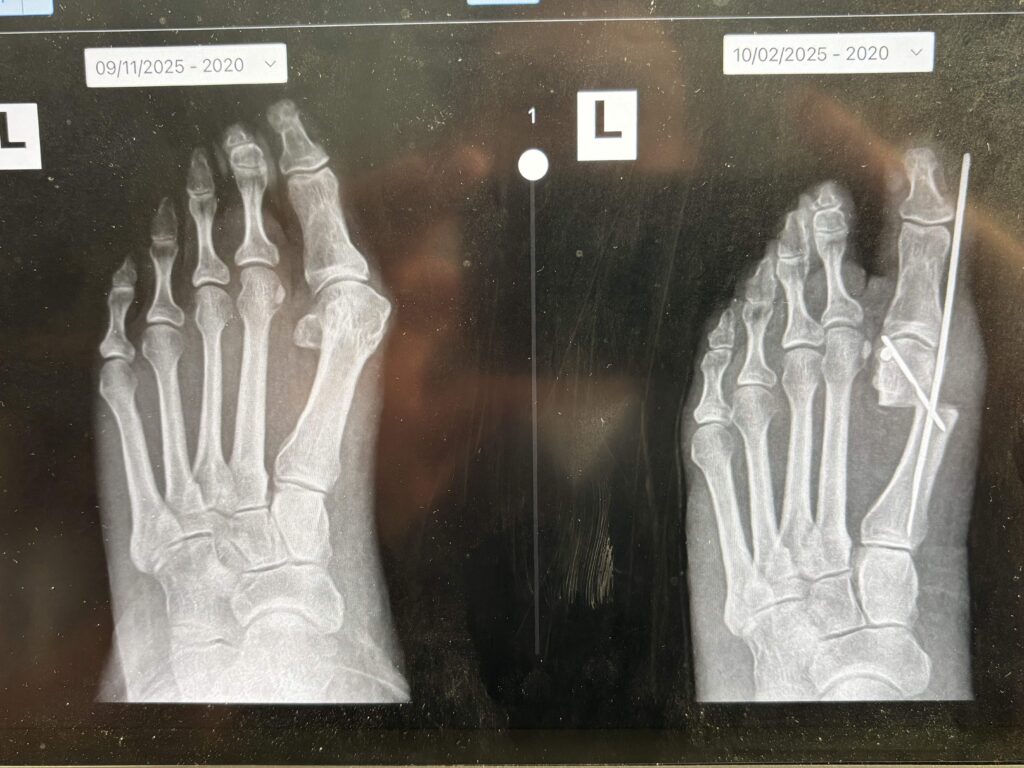

The only way to know for sure is through an in-person evaluation. Dr. Gateley will examine your foot, review weight-bearing X-rays, and have an honest conversation about which approach will give you the best outcome.

Dr. Gateley makes several tiny incisions — about the size of a pencil eraser — to access the bone. Using specialized instruments, he carefully cuts and repositions the bone to correct the alignment of your big toe. Depending on your case, the bone is secured with 2 pins to allow the bone to heal in its corrected position.

Sutures (if used) are typically removed around day 10 to 14, and Dr. Gateley will take X-rays to confirm the bone is healing properly.